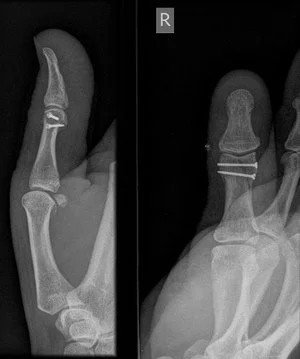

Tim Heath is a consultant hand surgeon at Eastern Suburbs Sports Medicine Centre and the principal surgeon at Southern Hand Surgery. He is a specialist with broad expertise in hand and wrist surgery: carpal tunnel syndrome, tendonitis and trigger finger, Dupuytren's disease, tumours and ganglions, microsurgery, fractures, arthritis, and wrist arthroscopy.